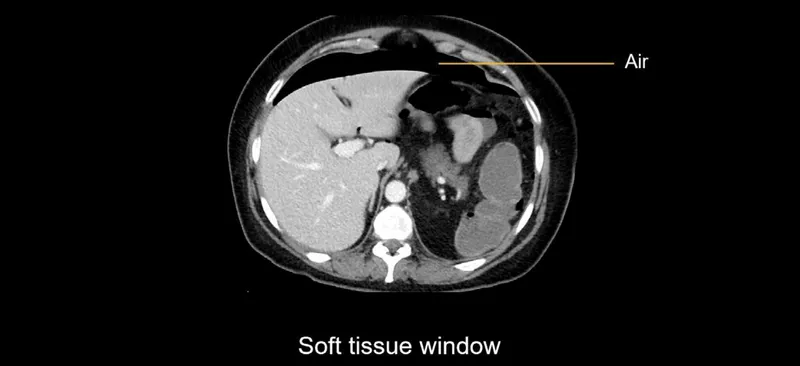

- Visceral Perforation: Free air under the diaphragm on imaging.

- Pneumoperitoneum on imaging is a classic sign of hollow viscus perforation requiring laparotomy.